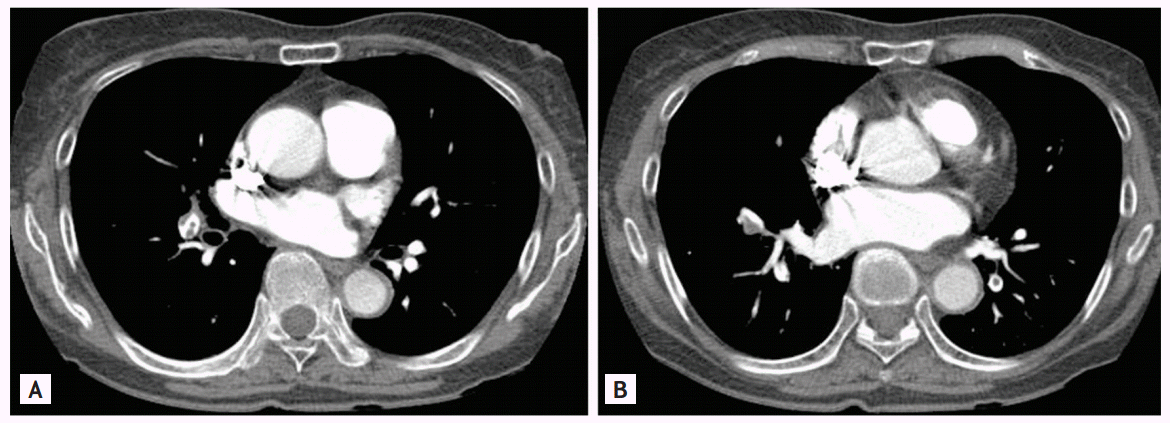

Cervical spine magnetic resonance imaging showed that both cord compression and stenosis were absent, but upper extremity angiography revealed severe stenosis of both the subclavian and axillary arteries (Fig. 1). Arteries distal to the site of stenosis, including the brachial, radial, and ulnar arteries, exhibited decreased blood flow, with the development of collateral arteries in the surrounding region. CT aortography revealed uptake by the walls of both the thoracic and abdominal aortas, suggestive of a large-vessel vasculitis such as TA. A pulmonary embolism was also accidentally found. FDG-PET/CT was performed after injection of 12.1 mCi 18F-FDG to assess the vasculitis. Linear distinct FDG uptake was evident in both the subclavian and axillary arteries (maxSUV, 2.2), and the ascending aorta and aortic arch (maxSUV, 2.1), indicating vasculitis (Fig. 2). We found no evidence of malignancy. Although she denied any symptom of dyspnea, a pulmonary embolism was found by chance. CT revealed multiple embolisms of both pulmonary arteries (Fig. 3). The anti-cardiolipin antibody immunoglobulin M (IgM) titer was 14.10 IgM phospholipid (MPL) units (normal range, < 7.0). The anti-β2 glycoprotein-1 antibody IgM titer was 22.0 U/mL (normal range, < 5), and the anti-lupus anticoagulant antibody titer was 1.91 (normal range, 0 to 1.24). The level of protein S was 54.5% (normal range, 50.8 to 116.9), the level of protein C was 173% (normal range, 70 to 148), and the level of antithrombin III was 120% (normal range, 65 to 129). On follow-up blood tests run 12 weeks later, she was positive for anti-cardiolipin antibody IgM, at 11.80 MPL units (normal range, < 7.0).

Figure 2.

(A) Fusion-coronal and (B, C) coronal images obtained by positron emission tomography (PET). Fluorine-18-fluorodeoxyglucose (FDG)-PET/computed tomography reveals stenosis of both subclavian arteries (A, arrows), and mild linear FDG activity along the wall of the aortic arch (B, arrowhead) and the descending thoracic aorta (C, arrowhead). Such activity is indicative of active vasculitis.